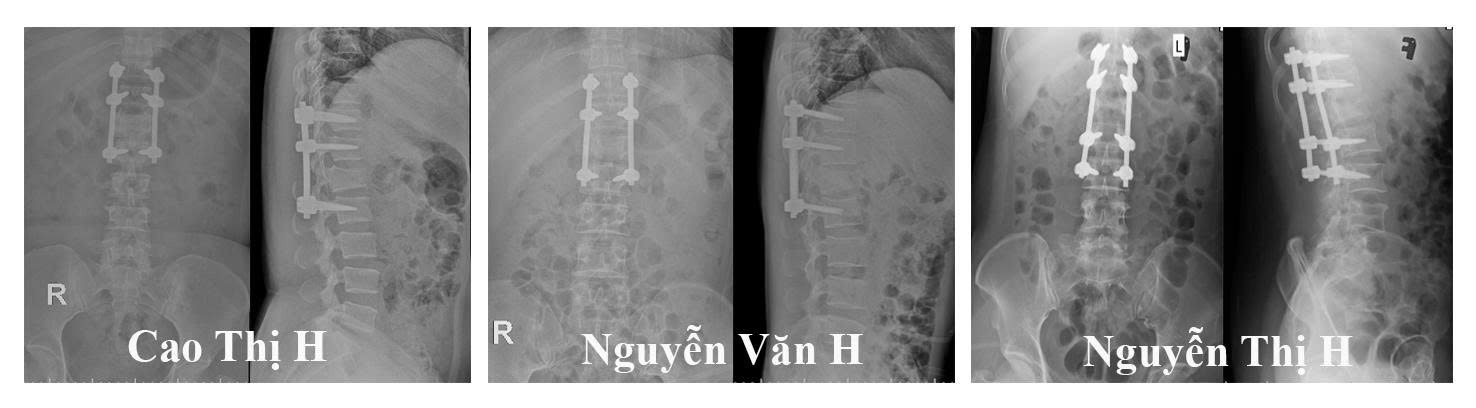

Các bệnh nhân nhập viện trong tình trạng đa chấn thương nặng sau tai nạn ngã từ độ cao khoảng 5m. Qua thăm khám lâm sàng, chẩn đoán hình ảnh và đánh giá đa chuyên khoa, cả 05 bệnh nhân đều được xác định có chấn thương cột sống, vỡ khung chậu, vỡ xương gót với mức độ khác nhau.

Đáng chú ý có 03 bệnh nhân tổn thương nghiêm trọng, có chèn ép tủy sống, mất vận động, rối loạn cảm giác và cơ tròn đã được chỉ định phẫu thuật cấp cứu, tiến hành cố định cột sống và giải ép tủy. Sự chuyên nghiệp của kíp mổ và kíp hồi sức được phụ trách bởi BS CK2 Ngô Văn Thành (khoa phẫu thuật thần kinh cột sống), BS CK2 Lê Văn Dũng (khoa gây mê hồi sức), BS CK2 Lương Mạnh Hùng (khoa hồi sức ngoại) các ca mổ được triển khai khẩn trương nhằm giải quyết nhanh chóng tổn thương thần kinh và mất vững cột sống.

Hình ảnh phim chụp cắt lớp vi tính của các bệnh nhân sau mổ